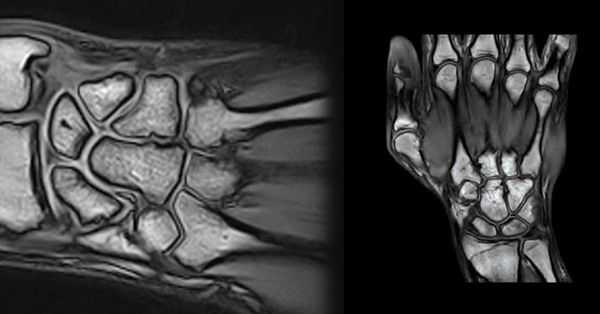

Схема, фронтальная плоскость: четыре отдельные суставные полости запястья. Дистальный лучелоктевой сустав отделен от лучезапястного сустава интактным треугольным фиброзно-хрящевым комплексом (ТФХК). Лучезапястный сустав отделен от среднезапястного (межзапястного) сустава ладьевидно-полулунной, полулунно-трехгранной связками и суставной капсулой. В редких случаях гороховидно-трех-гранный заворот образует самостоятельный отдел. Среднезапястный сустав обычно сообщается с 2-4 запястно-пястными суставами и соответствующими межпястными суставами. Первый запястно-пястный сустав отделен от остальных запястно-пястных суставов трапецие-пяст-ной связкой. Артрография лучезапястного сустава. Во фронтальной проекции визуализируется нормальный характер заполнения заворотов. Ладонный лучевой заворот не следует ошибочно принимать за ганглиозную кисту. В отличие от кисты он сообщается с полостью сустава через широкий перешеек. На фоне контрастного препарата определяются контуры интактного ТФХК, ладьевидно-полулунной и полу-лунно-трехгранной связок. Артрография лучезапястного сустава. В боковой проекции выявляются нормальные ладонный и тыльный завороты. Гороховидно-трехгранный заворот обычно сообщается с полостью лучезапястного сустава, но в редких случаях образует самостоятельный отдел. Седловидная суставная поверхность лучевой кости сочленяется с полулунной костью, которая в свою очередь имеет седловидную поверхность для сочленения с головчатой костью. Артрография среднезапястного пристального лучелоктевого суставов в передне-задней проекции. Препарат из среднезапястного сустава распространяется в общую запястно-пястную суставную полость. Первый запястно-пястный сустав от них отделен. Контрастный препарат, проходя между ладьевидной и полулунной костями, достигает уровня ладьевидно-полулунной связки, а проходя между полулунной и трехгранной костями-уровня полулунно-трехгранной связки. Данные связки отделяют среднезапястный сустав от лучезапястного сустава. После введения препарата в дистальный лучелоктевой сустав наблюдается его распространение между лучевой и локтевой костями, заполнение тыльного и ладонного заворотов. Контрастный препарат очерчивает ровный контур нижней поверхности треугольного фиброзно-хрящевого диска. МР-артрография в режиме Т1 ВИ, коронарный срез: после введения контрастного препарата в среднезапястный сустав определяется контур дистального края ладьевидно-полулунной и полулунно-трехгранной связок. Рисунок: показаны связки тыльной поверхности запястья. Внешние тыльные связки—тыльная лучезапястная, тыльная ладьевидно-трехгранная и тыльная межзапястная. Проксимальные внутренние связки—ладьевидно-полулунная и полулунно-трехгранная. Дистальные внутренние связки—трапецие-трапециевидная, трапецие-головчатая и запястно-пястная. Ладонная и тыльная дистальные лучелоктевые связки являются частью ТФХК. МР-артрография в режиме Т2 ВИ FS, коронарный срез: визуализируются фрагменты тыльных внешних связок. Рисунок ладонной поверхности запястья: показаны внешние и внутренние связки. Внешние ладонные лучезапястные связки: Лучеладьевидно-головчатая, длинная лучеполулунная, лучеладьевидно-полулунная и короткая лучеполулунная. Ладонные локте-запястные связки: локте-полулунная, локте-трехгранная и локте-головчатая. Ладонные среднезапястные связки: ладьевидно-трапецие-трапециевидная, ладьевидно-головчатая, трехгранно-головчатая и трехгранно-крючковидная. Проксимальные межкостные связки: ладьевидно-полулунная и полулунно-трехгранная. Дистальные межкостные связки: трапецие-трапециевидная, трапецие-головчатая, головчато-крючковидная и запястно-пястные. МР-артрография в режиме Т1ВИ FS, коронарный срез: визуализируются порции внешних ладонных связок. Рисунок проксимального ряда костей запястья: показаны шесть костно-фиброзных каналов, содержащих сухожилия разгибателей. На этом уровне сухожилие длинного разгибателя большого пальца перекрещивается с сухожилием короткого лучевого разгибателя запястья. В области перекреста сухожилие уплощено, что не следует ошибочно принимать за его поверхностный разрыв. Рисунок ладонной поверхности запястья: сухожилия сгибателей (влагалища удалены). Лучевой и локтевой сгибатели запястья лежат вне запястного канала. Рисунок тыльной поверхности запястья: сухожилия разгибателей. Сухожилие длинного разгибателя большого пальца (3-й тыльный отдел) на уровне дистального конца лучевой кости проходит по диагонали вместе с сухожилиями 1-го тыльного отдела.